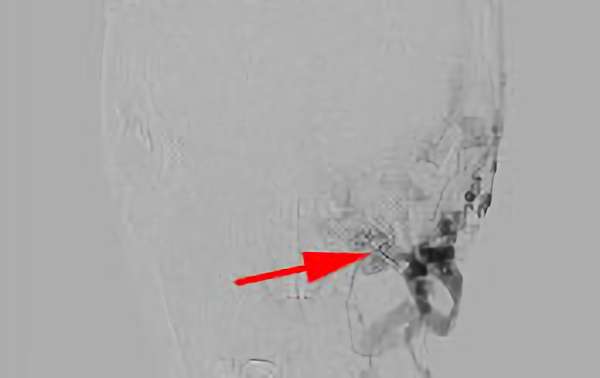

183

'18年7月17日

硬膜動静脈瘻

40代

大阪府の病院

中